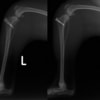

■ 症例22 ポメラニアン 1歳5か月 去勢雄

左後肢の挙上を主訴に来院した。整形学的検査、レントゲン検査より左右の膝蓋骨脱臼(左GradeⅡ〜Ⅲ、右Grade Ⅱ)を認めた。また、脛骨の前方引き出し試験の際に、引き出し兆候は認められないものの、疼痛が認められたため、前十字靭帯の損傷が疑われた。術中における、目視および関節内の操作によって、前十字靭帯の損傷や過伸展といった異常が認められなかったため、膝蓋骨脱臼の整復のみ実施した。手術手技は縫工筋及び内側広筋の解放、脛骨粗面の外側転位、滑車ブロック形造溝術、内外側関節包の縫縮を実施した。本症例は跛行もなく経過良好である。しかし、頸骨高平部の角度(TPA)が 右26.2°、左24.9°であり、解剖学的に前十字靭帯損傷のリスクが高いことから今後の経過に注意が必要である。